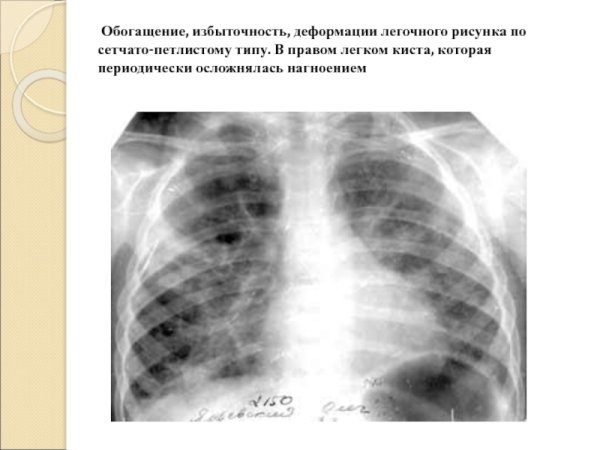

Деформированный легочный рисунок - это состояние, при котором наблюдается изменение обычного внешнего облика легких на рентгенограмме. Такое отклонение может быть связано с различными заболеваниями и патологическими процессами, такими как хронические обструктивные заболевания легких, фиброз, опухоли или воспалительные процессы. Деформированный легочный рисунок может представлять собой уменьшение объема легочной ткани, нарушение архитектуры легочных сосудов или изменение контуров легочных полей. Раннее выявление и диагностика таких изменений могут помочь в раннем начале лечения и улучшении прогноза для пациента.

Сетчатая деформация легочного рисунка рентген